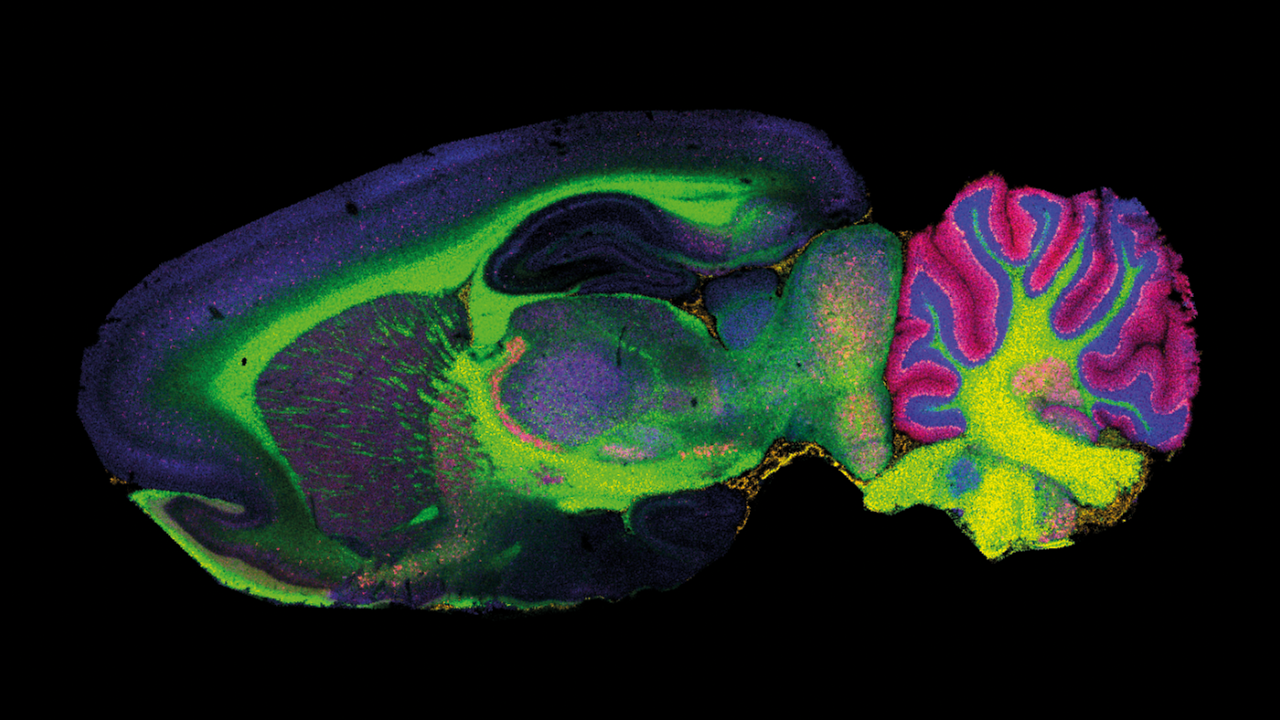

Four proteins distributed in rat brain. Two insets show protein ion Images overlaid with histology image. Note the strong localization to sub-structures.